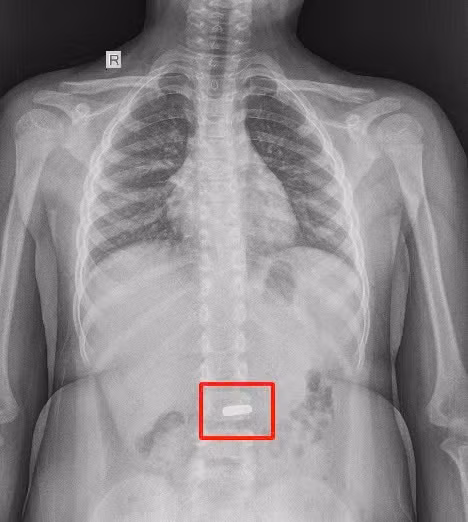

Tại bệnh viện, bé được thăm khám và chụp X-quang. Hình ảnh ghi nhận trong dạ dày có dị vật là nam châm với cạnh dài khoảng 20mm.

Phim chụp dạ dày có dị vật là nam châm với cạnh dài khoảng 20mm - Ảnh BVCC